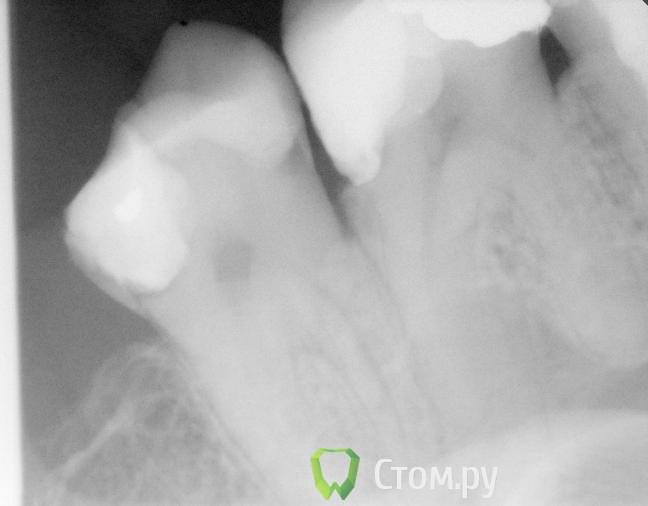

Ferny Опубликовано 9 ноября, 2011 Поделиться Опубликовано 9 ноября, 2011 через пол часа клиент придет. Помогие советом. жалобы на боль при сжатии зубов. а также на сладкое было пару раз. зубы 26 и 27- когда дула воздухом между двумя этими зубами..то было больно. Так дыруи не видно и зонл никуда вроде не застревает. Гдк она может быть. Ссылка на комментарий

Каплан Опубликовано 9 ноября, 2011 Поделиться Опубликовано 9 ноября, 2011 тут что?http://s41.radikal.ru/i094/1111/ba/d3d0ee2e1e47.jpg Ссылка на комментарий

victor57 Опубликовано 10 ноября, 2011 Поделиться Опубликовано 10 ноября, 2011 именно там Ссылка на комментарий

zybnaya feya Опубликовано 10 ноября, 2011 Поделиться Опубликовано 10 ноября, 2011 26 периодонтит,27 вторичный кариес Ссылка на комментарий

Ferny Опубликовано 10 ноября, 2011 Автор Поделиться Опубликовано 10 ноября, 2011 я в 27 зубе высверлила часть пломбы и там был кариес когда он ко мне первый раз пришёл, то жаловался на тупую боль при сжатии зубов. а так же на боль от сладкого и воздуха *когда я дула) ...после первого визита ко мне боль у него была постоянная, потом он принял ибупрофен и боль прошла и досих пор не возвращалась, видимо действительно тогда26 периодонтит,27 вторичный кариес Ссылка на комментарий